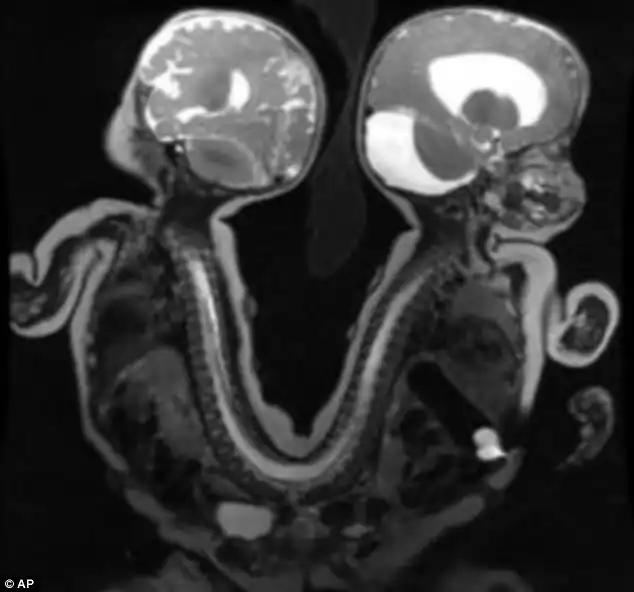

Темнокожие мальчики Иисус и Иаков родились на свет соединенными спина к спине в области таза и нижней части позвоночника. Часть желудочно -кишечного тракта у них тоже была общей. В остальном же они были полностью функциональны и здоровы.

Провели сложную 13-часовую операцию еще 29 августа и на данный момент разделенные дети чувствуют себя очень хорошо и впервые могут увидеть друг друга в лицо.